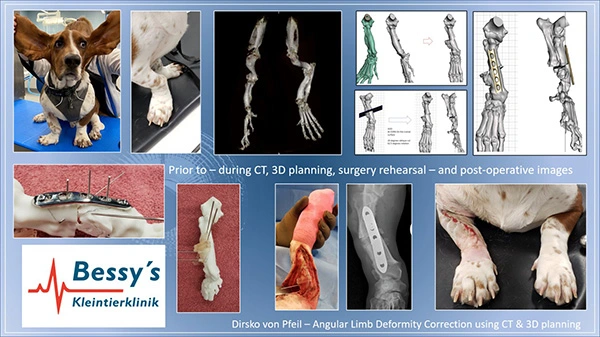

Knochendeformation

Knochendeformation und deren Korrekturen

Erfolgt typischerweise mit 3D-Rekonstruktion basiered auf computertomographische Untersuchung, sowie spezieller Planung mit Knochenmodellen.

Hierbei korrigieren wir Knochen- oder Gelenkdeformationen mithilfe von exakten Knochenmodellen, die speziell auf den knöchernen Defekt des individuellen Patienten hergestellt werden.

Korrektur einer extrem verdrehten Vordergliedmasse (links oben). Computertomographie (Mitte), 3D Planung (rechts oben), Operations-planung, und Durchführung (links unten bis Mitte). Ansicht nach der Operation zeigt deutliche Verbesserung.